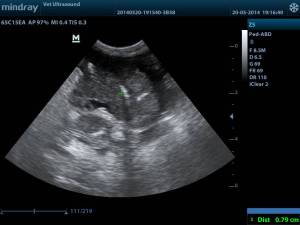

πάχος την μάζας 0.79 cm, φυσιολογικό πάχος λεπτού εντέρου 0.2 -0.3 cm